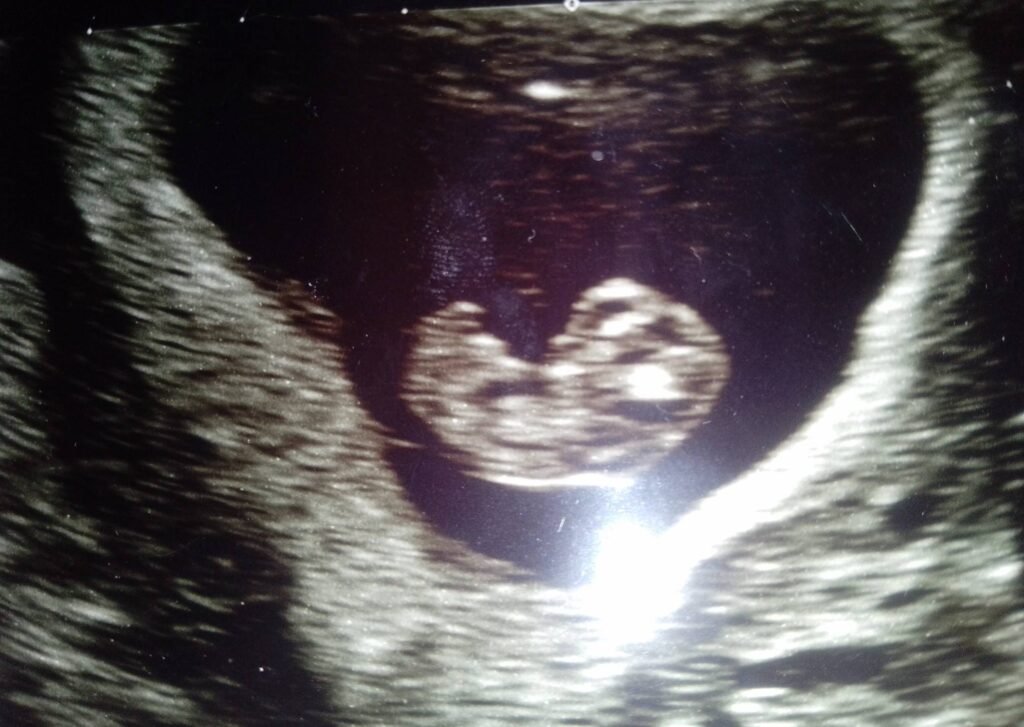

© Alexandra Chambers | Neurotopia CIC | January 2026 During my first pregnancy, the foetus remained in breech position throughout. As I approached term, NHS clinicians became increasingly insistent on scheduling an external cephalic version (ECV) – a manual procedure to turn the baby into a head-down position. I declined because I had a deep, […]